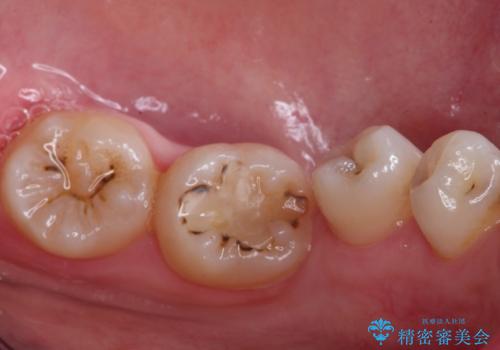

歯並びの改善とインプラントでのかみ合わせの回復 インプラント・セラミック・矯正全顎治療

- 歯医者が怖くて悪い歯をそのままにしてしまった、悪いところを治したいとのことで来院されました。

虫歯の歯や、歯を抜いてしまったところをそのまま放置していたことにより、歯並びも悪くなっていました。

矯正をはじめ、根の治療・インプラント・セラミックによる全体治療を提案させていただき、治療をしていくこととなりました。